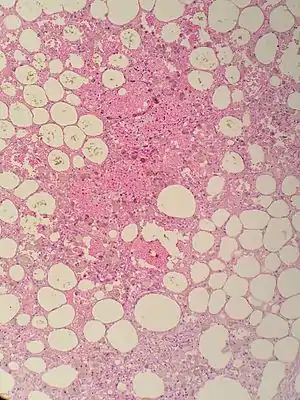

| Sclerosing mesenteritis - note the hemosiderin, chronic inflammation | |

The disorder is identified by histopathology showing fat necrosis, fibrosis and chronic inflammation of the small intestine. Examination of the mesentery may indicate a solitary mass, but diffuse mesentery thickening is common.[4][6]